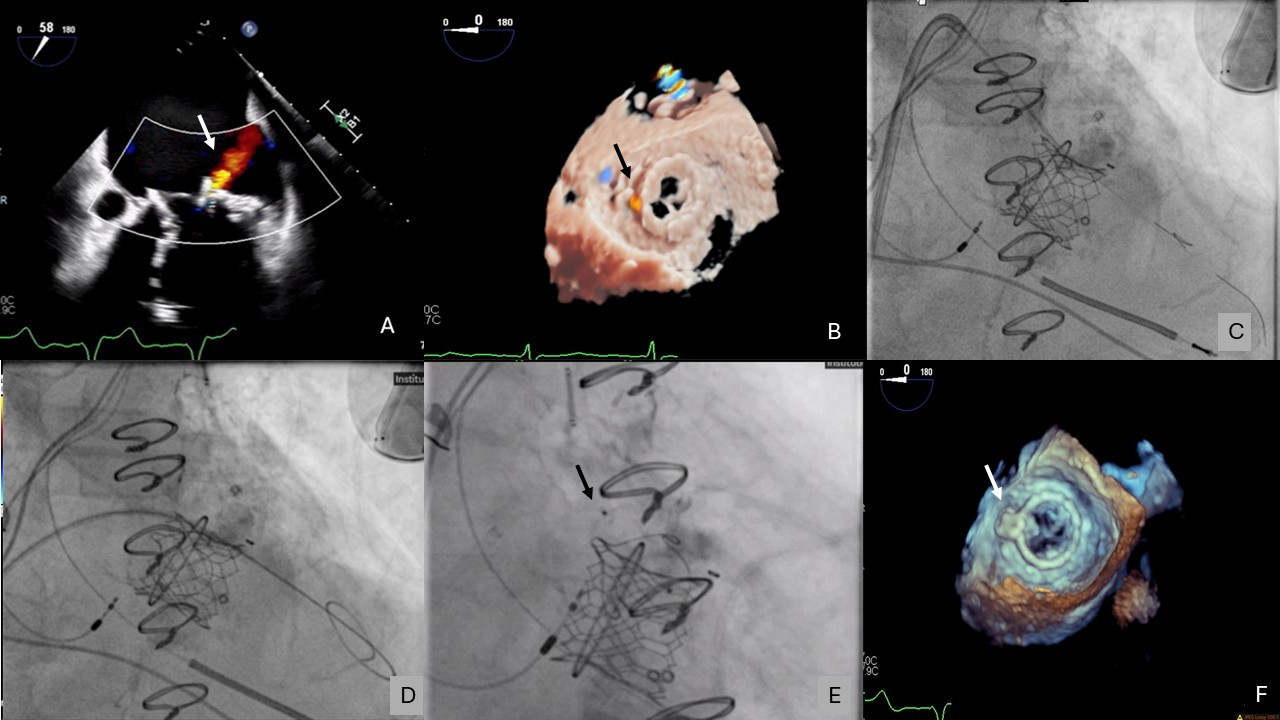

An 86-year-old man who had undergone recent transcatheter mitral valve-in-ring at an outside hospital presented with multiple hospitalizations for symptomatic hemolytic anemia requiring blood transfusions. Transesophageal echocardiogram (TEE) demonstrated mitral paravalvular leak (PVL) originating laterally between the transcatheter valve and surgical ring (Figure 1A and B, Video 1).

The patient underwent transcatheter mitral PVL closure. A 14F Dryseal sheath (Gore Medical) was inserted into the right femoral vein. A catheter was advanced across the pre-existing atrial septal defect into the left atrium and was exchanged for an 8.5F Agilis sheath (Abbott) over a Confida wire (Medtronic). A 6F multipurpose catheter, a 4F angled glide catheter, and an angled Glidewire (Terumo) were advanced into the Agilis.

The Glidewire successfully crossed the PVL and advanced into the left ventricle (LV), but the 4F angled glide catheter could only partially cross the defect. The angled Glidewire was exchanged for 2 Grand Slam coronary wires (ASAHI INTECC) (Figure 1C). The 4F angled glide catheter was exchanged for a 5F tapered catheter, which was successfully advanced into the LV. The Grand Slam wire was exchanged for the Confida wire (Video 2).

The 6F multipurpose catheter could not advance across the PVL. The 8.5F Agilis and 6F multipurpose catheters were exchanged for a Flexor Shuttle sheath (Cook Medical), which also could not cross the PVL. A 6F Radial to Peripheral (R2P) sheath (Terumo) was successfully advanced across the PVL (Figure 1D). A 6 x 6-mm Amplatzer Duct Occluder II (ADO II) (Abbott) was advanced through the R2P sheath and deployed. After TEE demonstrated significant reduction in the PVL, the Confida wire was retracted into the R2P sheath and the device was released (Figure 1E, Video 3).

Postprocedural TEE demonstrated complete resolution of the PVL (Figure 1F, Video 4). The patient was discharged home the following day with stable hemoglobin at follow-up.